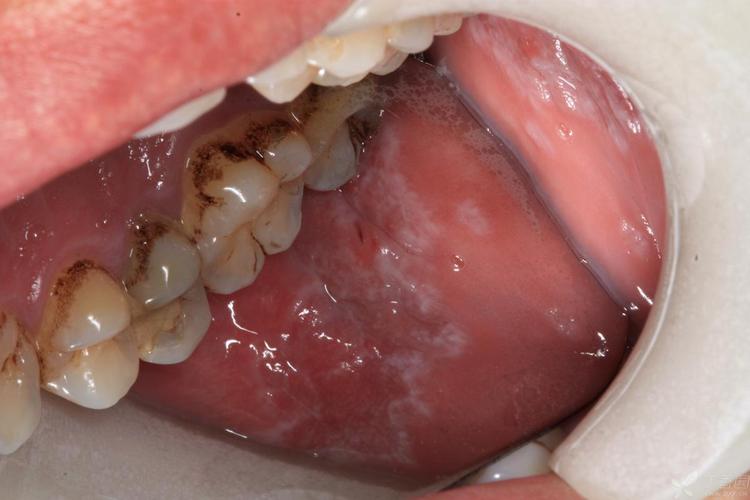

口腔扁平苔藓饮食禁忌有哪些?

(图片来源网络,侵删)